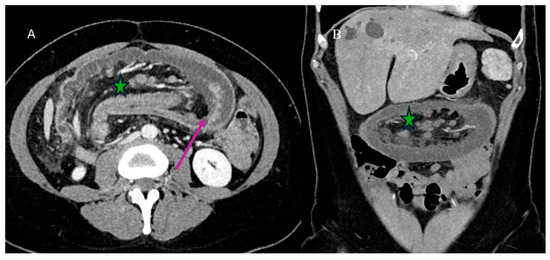

2.5. Small Bowel Tumors Presenting with Bleeding, Ischemia, and Perforation